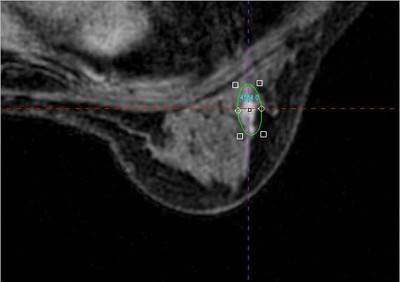

圖片說明:AURORA乳房專用MRI之3D影像讓乳房微小病灶無所遁形

C小姐是50歲國中老師(個案基本資料經虛擬修改),過去一年來不覺得身體有任何不舒服或變化,因學校例行的健康檢查有機會接受本院高階乳房專用磁振造影檢查,檢查後醫師經由影像分析向C小姐說明乳房健康狀況,C小姐本以為自己可以得到「一切正常」的答案,沒想到醫師竟然告知從影像中發現左乳有一可疑的顯影,而且極可能是不好的病灶,當天檢查完成後醫護人員立即為C小姐安排至乳房外科門診進一步診療,但是外科的門診時間到了,C小姐卻沒有出現,後來透過本中心醫療人員的電話關心,發現她正處於「疾病否認期」,醫療人員擔心C小姐因逃避現實而錯過治療的黃金時期,經持續對她耐心說明和安撫後,C小姐同意先到乳房外科門診聽聽專業醫師的建議。C小姐希望醫師告訴她最徹底的解決方式以免除她因等待確診結果而提心吊膽,醫師解釋因為C小姐病灶較小,建議使用乳房專用磁振造影鋼針定位切除術,以免切除位置不精準而有殘餘癌的風險。手術後,病理結果證實是「乳小葉原位癌」,C小姐心裡雖然難過,但是慶幸可以透過此次健檢所安排的乳房專用磁振造影檢查早期發現原位癌得到即時的治療,她更是感謝醫療人員為了她的健康,盡心盡力的安排後續解決方法,讓她能安心的接受手術。